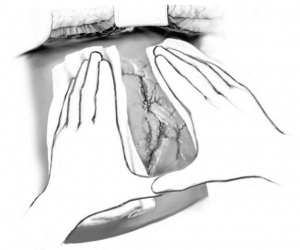

Trường hợp máu đã ngừng chảy thì chỉ cần lấy máu cục quanh gan, rửa sạch ổ bụng, đặt dẫn lưu (nếu cần). Trường hợp chảy máu nhiều từ gan có thể cầm máu tạm thời bằng cách ép gan bằng tay (Hình 2), ép gan với hai tay và ép vào cơ hoành, giao cho người phụ giữ, kiểm soát cuống gan toàn bộ (thủ thuật Pringle) (Hình 3), nhanh chóng thăm dò ổ bụng để loại trừ các nguồn chảy máu khác.

Hình 2. Kỹ thuật dùng tay ép nhu mô gan cầm máu tạm thời